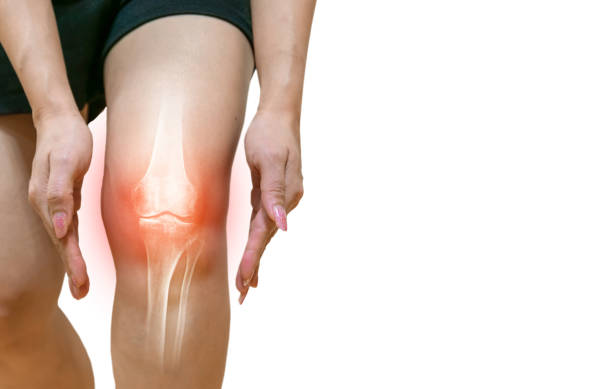

무릎 통증 원인 초기 치료 자세히 알아보기

무릎 통증이 초기에 발견되고 적절한 치료를 받으면, 심각한 상태로 악화되는 것을 예방할 수 있습니다. 무릎 관절은 몸의 중심부에 위치하고 있어, 무게 중심의 일부를 지지하며, 매우 복잡한 기구로 구성되어 있습니다. 따라서 무릎 관절의 이상은 다양한 원인과 증상을 보일 수 있습니다. 초기에 발견하여 조치를 취하지 않으면, 무릎 관절은 더 큰 문제로 발전할 수 있어 이번 시간에는 무릎 통증 원인과 초기 치료에 대해 알아보겠습니다.

연골손상에 의한 무릎 통증

연골은 뼈와 뼈 사이의 마찰을 줄이고 충격을 흡수하는 기능을 합니다. 무릎의 연골손상은 무릎 통증의 일반적인 원인 중 하나입니다. 연골손상은 다양한 원인으로 발생할 수 있으며, 가장 흔한 원인은 무릎 관절 내의 충격이나 비대칭적인 압력에 의해 발생하는 외상입니다. 연골손상은 통증, 부종, 불안정성, 감각 손실 등의 증상을 일으킬 수 있습니다. 치료는 무릎 관절을 안정시키는 운동, 연골 재생을 촉진하는 약물 치료, 수술 등이 있습니다.

전방십자인대 파열에 의한 무릎 통증

전방십자인대는 무릎을 지탱하는 중요한 인대 중 하나입니다. 이 인대가 파열되면 무릎이 불안정해지며, 걷거나 달리는 등의 운동 시 무릎이 흔들리거나 무력감이 느껴집니다. 무릎 통증, 부종, 불안정감 등의 증상이 나타나며, 복합적인 치료가 필요합니다. 치료에는 수술적 치료, 전문가의 지도하에 진행되는 재활 운동 등이 포함됩니다.

슬개골염에 의한 무릎 통증

슬개골염은 슬개골 연골과 연결된 퇴행성 질환으로, 무릎 관절 내부에서 연골의 변성이 진행됨에 따라 발생합니다. 무릎 통증, 관절 강직, 충수성 부종 등의 증상을 일으키며, 보행이나 운동 시 통증이 더욱 심해질 수 있습니다. 치료는 운동 치료, 약물 치료, 수술적 치료 등이 있으며, 초기 단계에서 조기에 진단하고 치료를 시작하는 것이 중요합니다.

무릎 관절염에 의한 무릎 통증

무릎 관절염은 무릎 관절의 연골과 주변 조직들이 염증을 일으키는 질환으로, 노화, 과부하, 외상 등이 원인이 됩니다. 무릎 관절이 불안정해지고 염증이 발생하면 통증, 부종, 관절 강직 등의 증상이 나타납니다. 운동, 체중 감량, 약물 치료 등이 치료 방법으로 사용됩니다. 특히 중증도가 높은 경우 수술 치료가 필요할 수 있습니다.